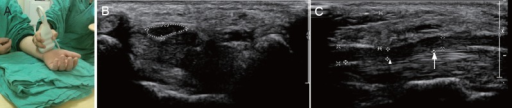

Cross-sectional anatomy of the carpal tunnel at the level of the hook of hamate. The median nerve lies superficially, just deep to the transverse carpal ligament (flexor retinaculum). The nine flexor tendons (4 FDP, 4 FDS, FPL) fill the tunnel. The median nerve is flattened and enlarged proximally. The thenar branch exits radially. Release involves dividing the transverse carpal ligament while protecting the nerve and palmar cutaneous branch.